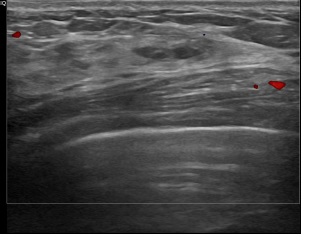

상기환자는 양성추정혹 추적관찰 하시는 40대중반

여성분으로 의심스러운 좌측혹 조직검사 시행해 으로 상피내암 진단되었습니다